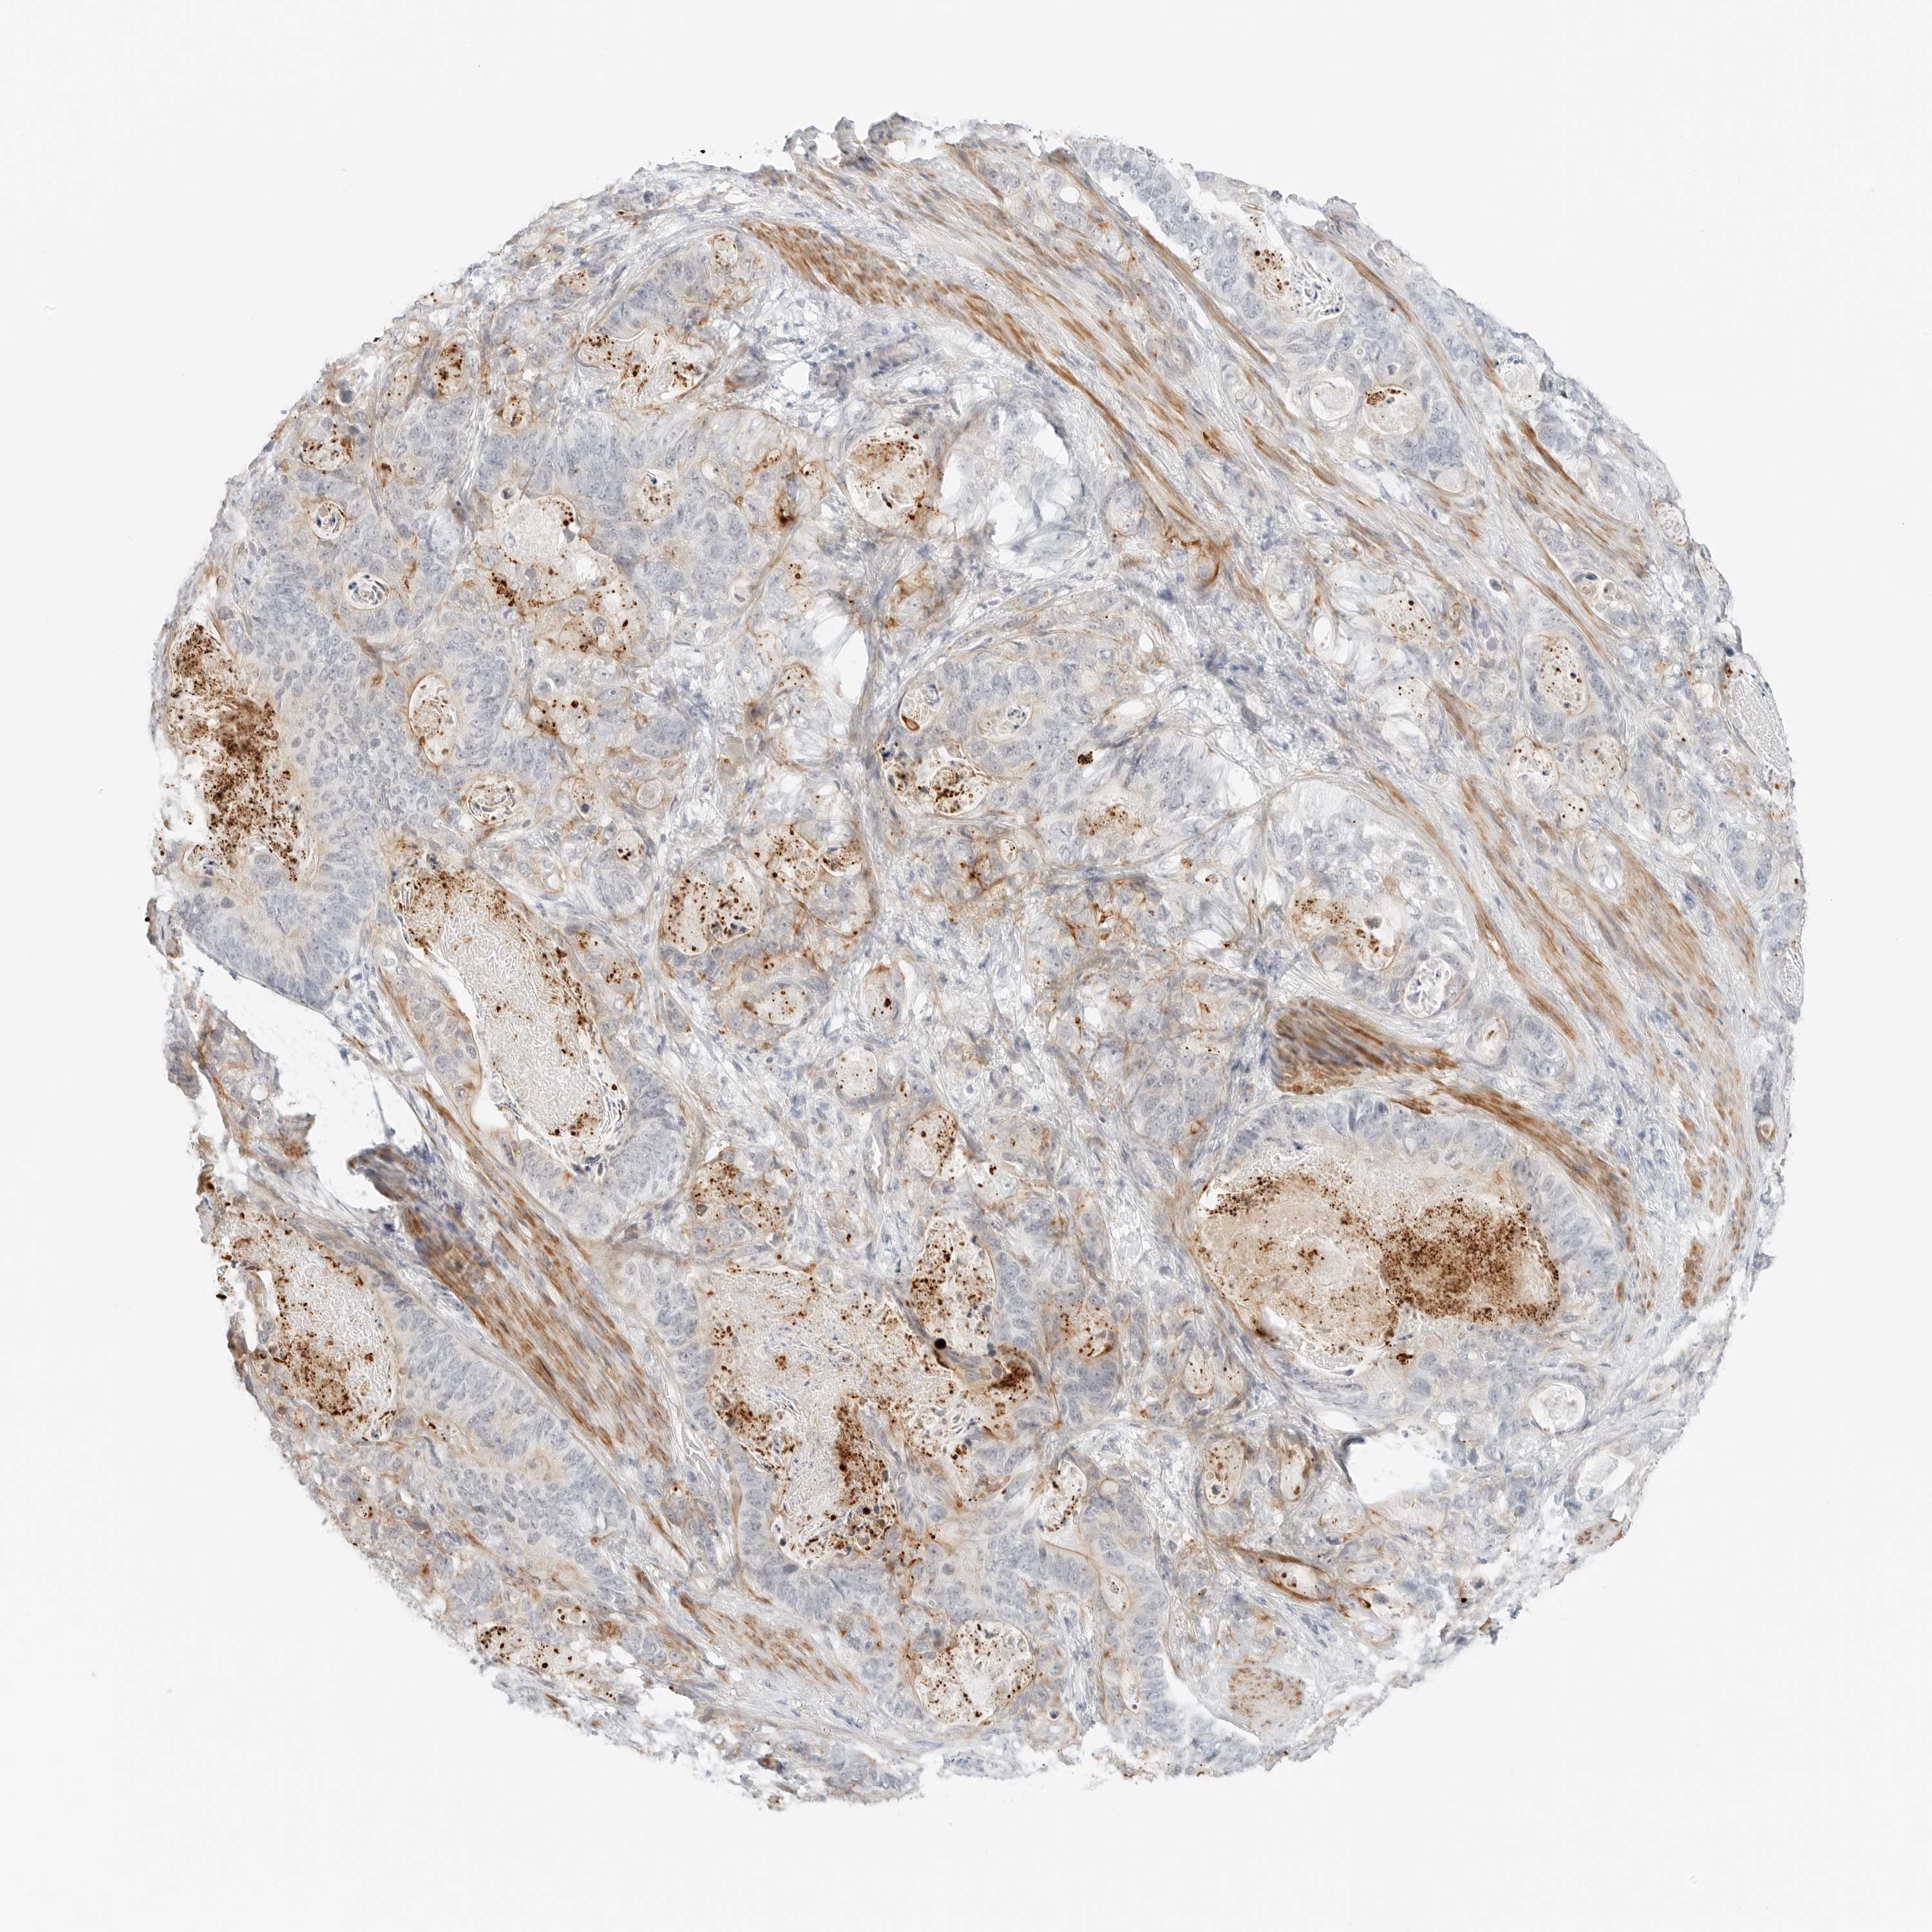

STOMACH CANCER - Protein expressioni

A mouse-over function shows sample information and annotation data. Click on an image to view it in a full screen mode. Samples can be filtered based on level of antibody staining by selecting one or several of the following categories: high, medium, low and not detected. The assay and annotation is described here.

Note that samples used for immunohistochemistry by the Human Protein Atlas do not correspond to samples in the TCGA dataset.

Antibody stainingi

Antibody staining in the annotated cell types in the current human tissue is reported as not detected, low, medium, or high, based on conventional immunohistochemistry profiling in selected tissues. This score is based on the combination of the staining intensity and fraction of stained cells.

Each image is clickable and will lead to virtual microscopy that enables deeper exploration of all samples and also displays staining intensity scores, fraction scores and subcellular localization as well as patient and tissue information for each sample.

Antibody HPA028602

Antibody HPA028686

Staining

High

Medium

Low

Not detected

Intensity

Strong

Moderate

Weak

Negative

Quantity

>75%

75%-25%

<25%

None

Location

Nuclear

Cytoplasmic/membranous

Cytoplasmic/membranous,nuclear

Adenocarcinoma, NOS